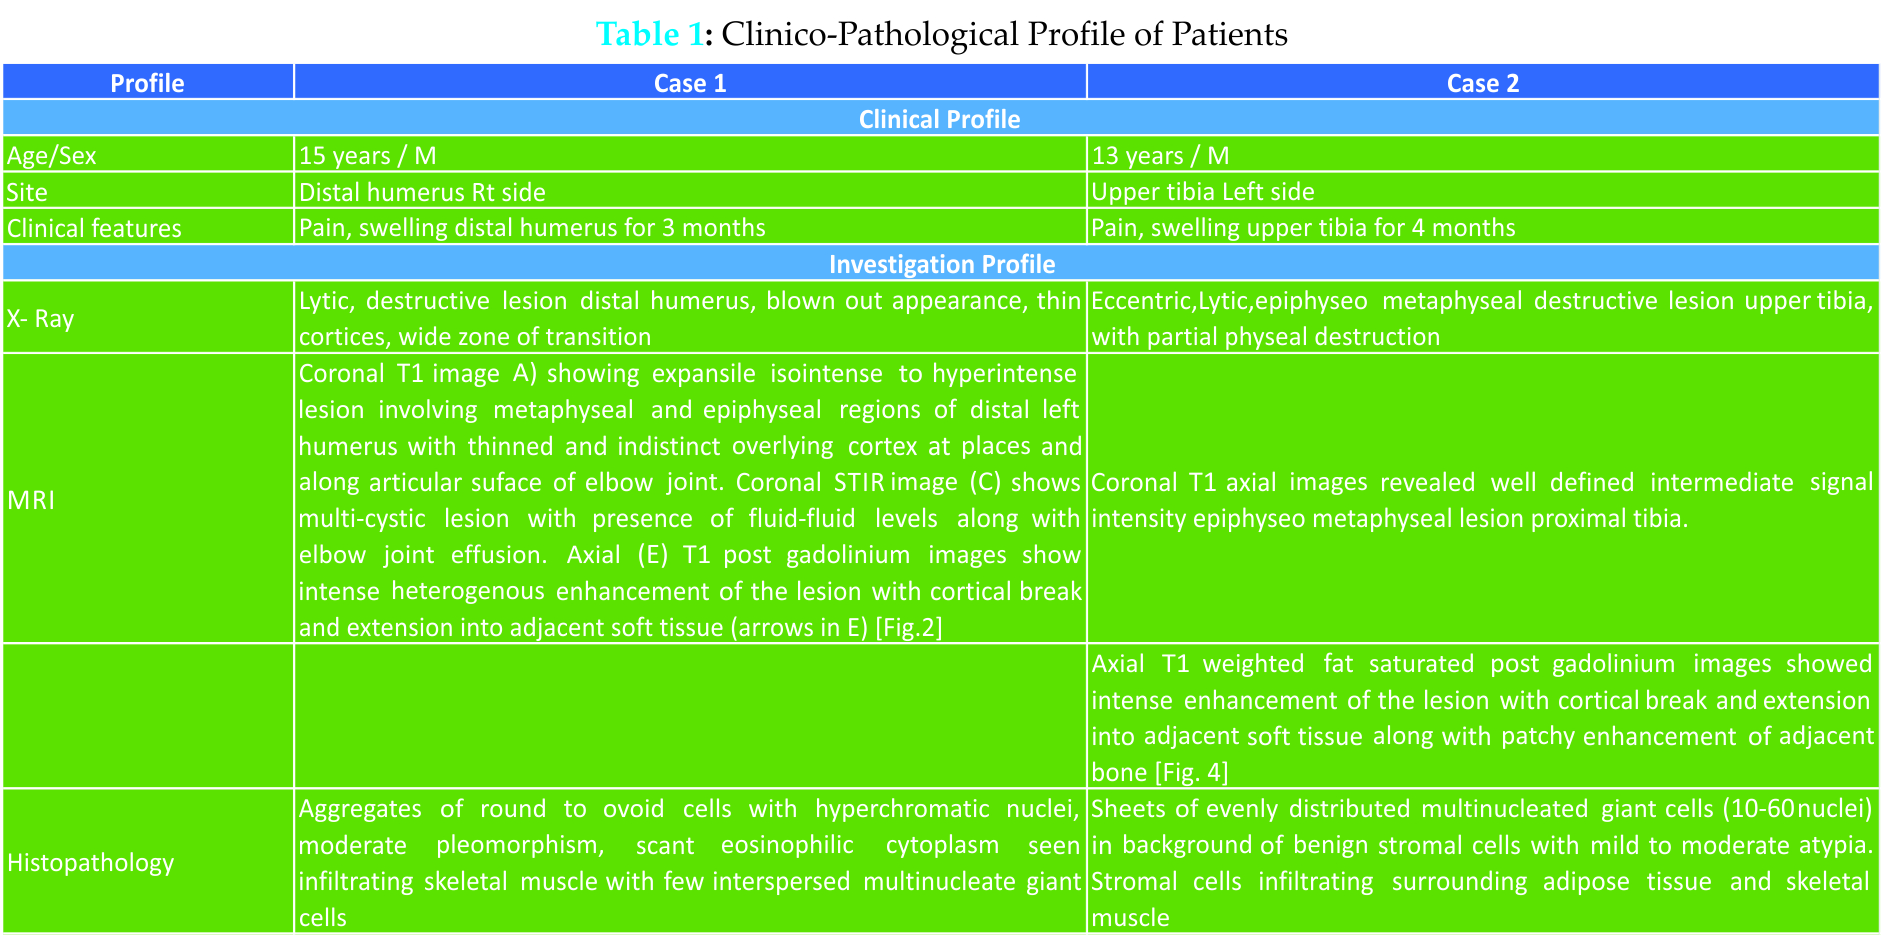

In our orthopaedic oncology clinic we have come across two pediatric patients having giant cell tumor of bone in last two years. First patient was a 15 years old male child presenting to us with history of pain, swelling in right distal humerus for last three months. Second patient was thirteen years old male who came with a history of swelling proximal tibia and painful ambulation for last four months. Their detailed clinicopathological profile is given in Table 1. There was no antecedent history of trauma or systemic disease. Radiologically features of epiphyseometaphyseal lesion, thinned out cortices, physeal destruction and wide zone of transition were noted more so in first patient. Keeping in view age of patients and radiological appearance differential diagnosis- of chondroblastoma, brown tumor, aneurysmal bone cyst and giant cell tumor were kept. Biochemical profile revealed normal serum alkaline phosphatase levels thereby excluding hyperparathyroidism. MRI in both patients was suggestive of GCT which was confirmed by histopathology examination.

There was no antecedent history of trauma or systemic disease. Radiologically features of epiphyseometaphyseal lesion, thinned out cortices, physeal destruction and wide zone of transition were noted more so in first patient. Keeping in view age of patients and radiological appearance differential diagnosis- of chondroblastoma, brown tumor, aneurysmal bone cyst and giant cell tumor were kept. Biochemical profile revealed normal serum alkaline phosphatase levels thereby excluding hyperparathyroidism. MRI in both patients was suggestive of GCT which was confirmed by histopathology examination.

Both patients had Campanacci grade III giant cell lesions and were managed surgically. As Case 1 had cortical breach in multiple planes, large soft tissue component, total physeal destruction, large area of subchondral bone involvement, hence wide resection with total elbow replacement was planned [Fig.1].

Case 2 had minimal cortical breach and a small soft tissue component. Hence this patient was managed by extended curettage, cementation and plate-screw construct augmentation. There was wound dehiscence at six weeks in this patient which was managed by gasrtrocnemius flap [Fig.3]. Both the patients are free of recurrence at one year follow up.